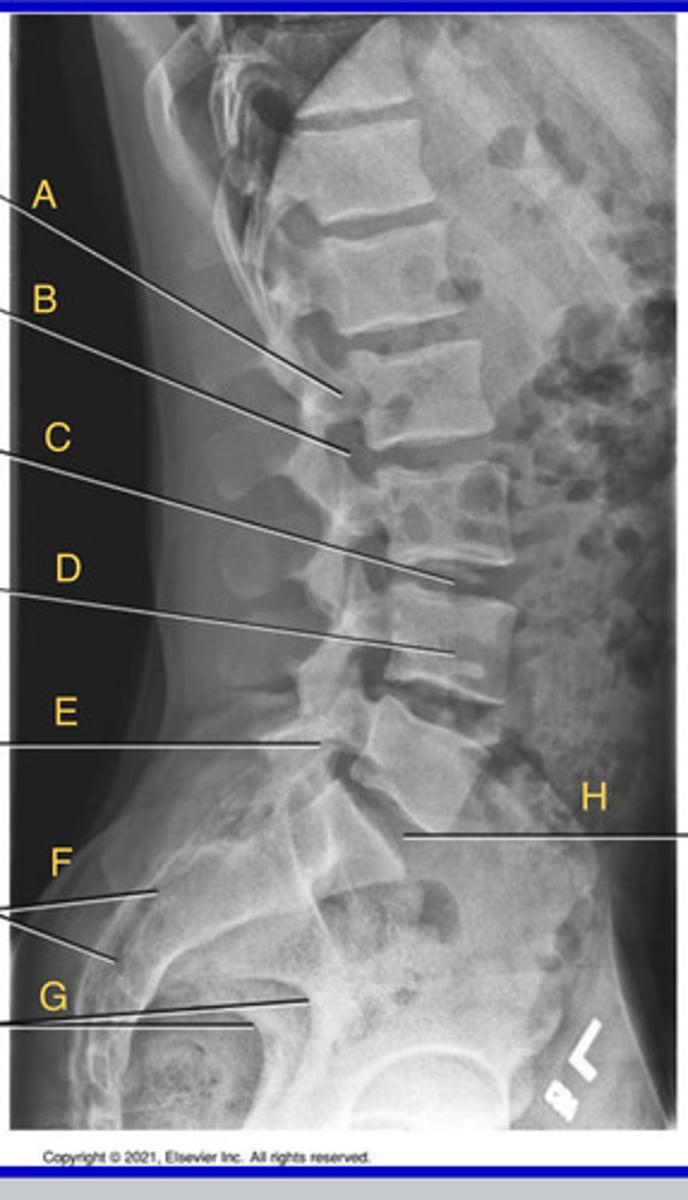

L2 Pedicle

A.

L2-3 intervertebral foramina

B.

L3-4 intervertebral joint space

C.

L4 body

D.

L5-S1 articular process

E.

Sacrum

F.

Greater sciatic notch

G.

L5-S1 joint

H.

Lateral Lumbar

What position?